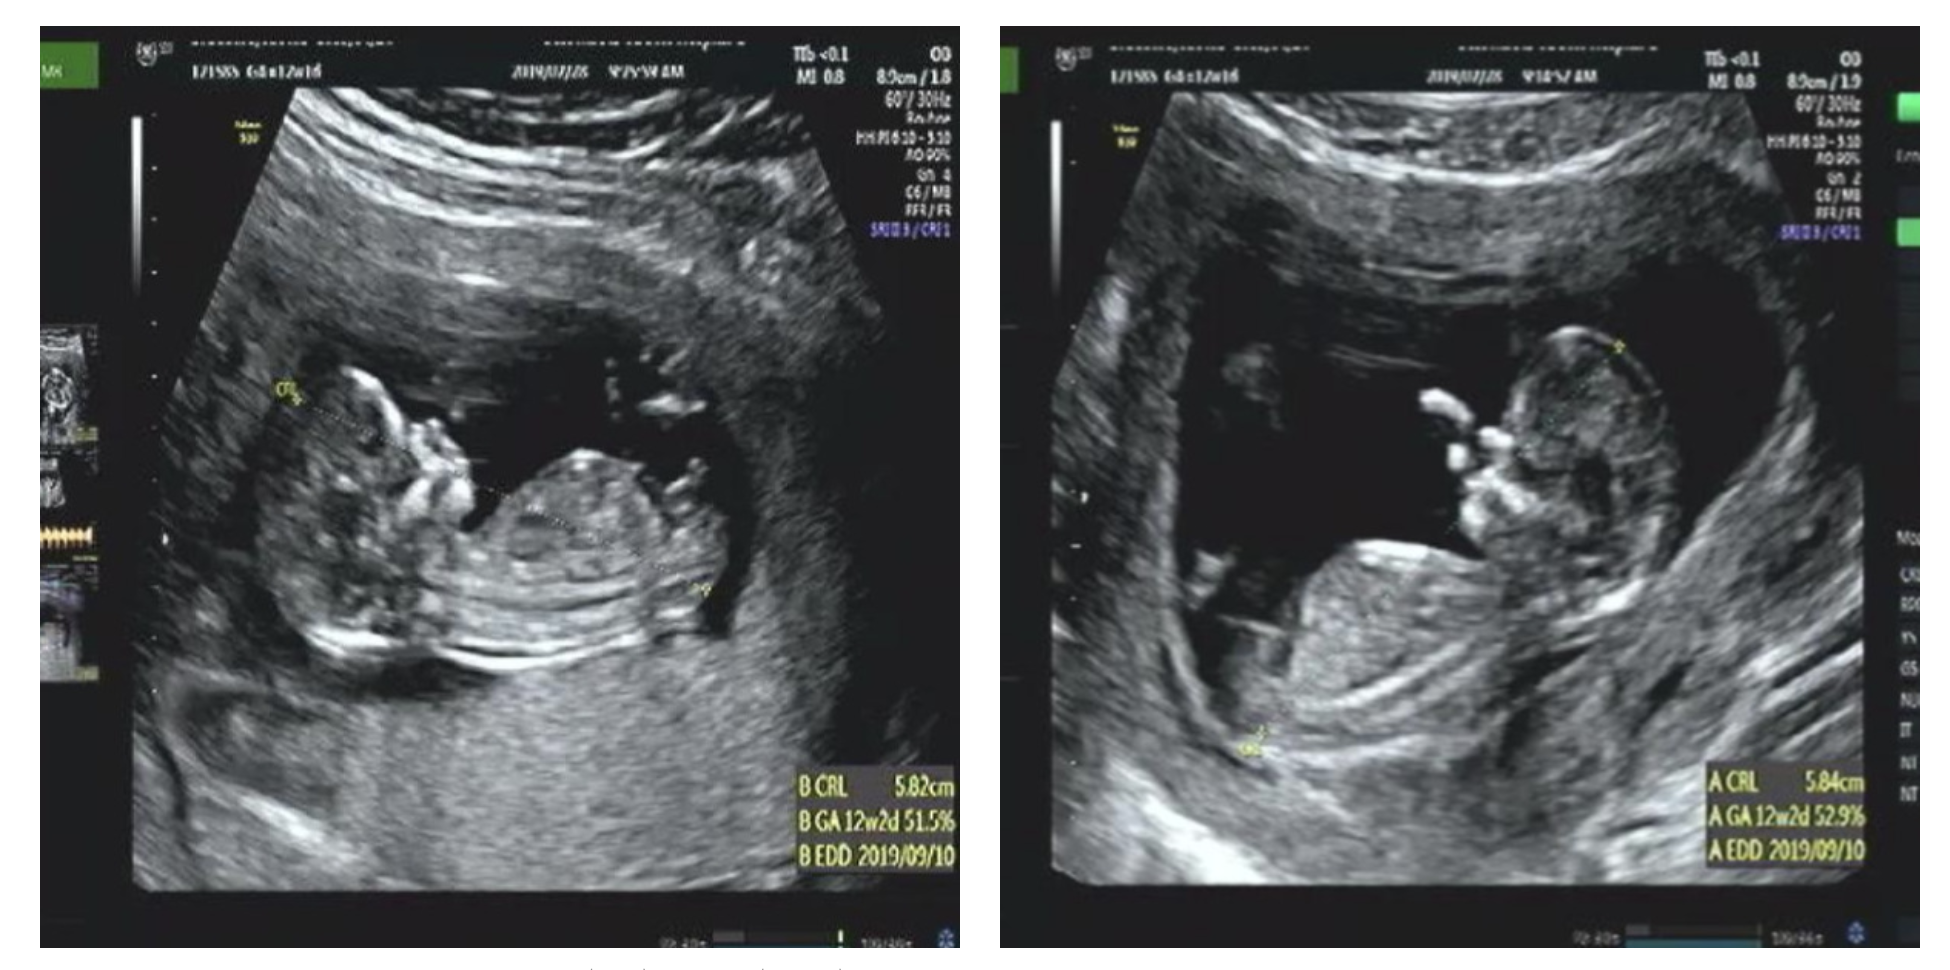

그와중에 귀엽다고 찍어주신 망고 발바닥 일란성 쌍둥이 중 15퍼센트 정도의 확률로 나타난다고 한다. 그 다음날 분당 서울대 진료를 봤다. 나는 원래 집에서 가까운 여성 병원에서 진료를 보다가 일란성 쌍둥이인걸 알고 분당 서울대로 전원하여 불과 일주일 전에 진료를 봤는데 그 때는 별 이상이 없었다. 담당 교수였던 박지윤 교수님이 이게 무슨 일이냐고 깜짝 놀라셨고 초음파 상으로 1기 정도 된다고 하셨다. 시술은 간단하지만 기계가 있는 병원이 아산, 서울대 본원 (그리고 지금은 부산 백병원까지) 뿐이라 아산이나 서울대 본원에서 시술을 받아야 한다고 했다. 그리하여 쌍둥이 나라 카페에서도 유명하고 방송에서 명의로도 소개된 원혜성 교수님이 계시는 아산 병원으로 가게 되었다. 참 고마운 것이 산모들에게 무슨 일이 있으면 병원 대표 전화가 아닌 분만장으로 전화하라고 한다. 나도 분만장으로 바로 전화해서 쌍태아 수혈 증후군이라고 하고 바로 다음날 외래를 잡았다.

지금 보면 12주때부터 포도(왼쪽)보다 망고(오른쪽)의 양수가 눈에 띄게 많다. 망고는 양수가 많아서 둥둥 떠 돌아다니는 바람에 심장 소리 듣기도 힘들었다. 전조 증상 (개인적 의견)